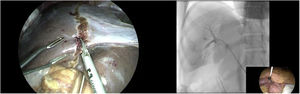

El video muestra el tratamiento de un paciente de 43 años con una lesión hipovascular sólida de 10cm, que involucra todo el lóbulo hepático derecho y el segmento IV con compromiso de la vena suprahepática derecha y media en íntimo contacto con la vena cava retrohepática. La volumetría preoperatoria del remanente hepático futuro (RHF) resultó en 360cm3 (22%). Se realizó un mini-ALPPS híbrido con embolización portal derecha intraoperatoria a través de la vena mesentérica inferior. A los 14 días, una volumetría demostró un RHF de 854cm3 (incremento del 237%). El día 21, se realizó trisectorectomía derecha con resección parcial de vena cava. El postoperatorio transcurrió sin incidencias y fue dada de alta al 5.° día de la cirugía. La histopatología mostró colangiocarcinoma intrahepático moderadamente diferenciado de 9cm con infiltración de vena cava y sin metástasis a ganglios linfáticos en 0 de 9 resecados (pT4N0M0, estadio IIIB del 8.° TNM) (fig. 1).